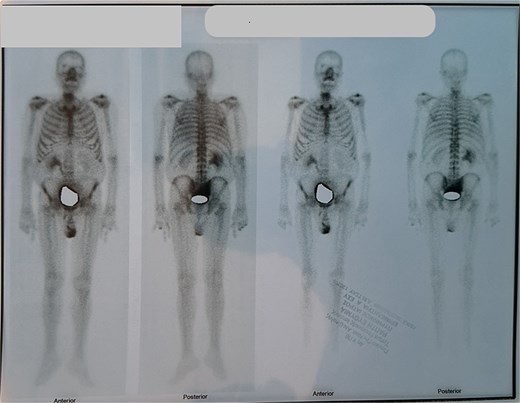

Due to improvement in his symptoms, the patient did not attend his three-month follow-up appointment. Eight months later, the patient was hospitalized with shortness of breath and multiple pulmonary nodules (Fig. 1) on the chest computed tomography (CT) in the pulmonology department of our hospital. Figures 2 and 3 show the preoperative chest X-ray and the chest X-ray taken eight months after the TURP, respectively. Suspected of metastatic disease, a urological evaluation was performed, which revealed an abnormal DRE and a significantly elevated PSA of 134 ng/ml. Diagnostic bronchoscopy and histological findings of the lung biopsy confirmed prostate adenocarcinoma (PCa). TRUS-Bx prostate biopsy (12 cores) confirmed the diagnosis of PCa with involvement of all prostatic cores and Gleason Score (GS) = 8 (4 + 4). Bone scan (Fig. 4) and CT scan were negative for other secondary metastatic lesions in bones and lymph nodes. The patient immediately started combination therapy ADT (degarelix) with apalutamide, and 3 months later, he was off oxygen, and his PSA level had decreased to 14.9 ng/ml.